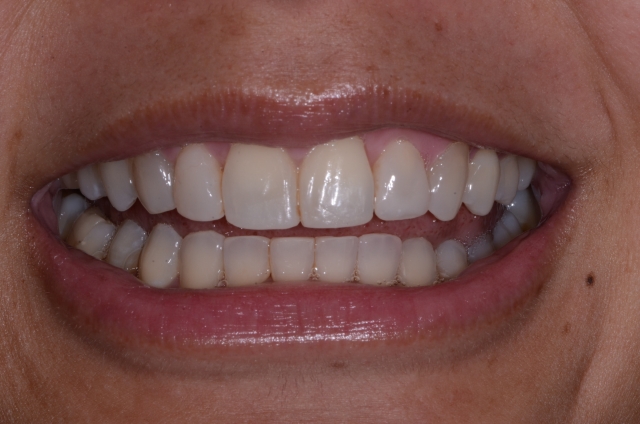

It’s then the orthodontist’s job to finish alignment of the teeth and make things look right, as you see in Fig. 9:

It’s important to note that this is the same bonding you saw in Fig. 8; the difference is that the teeth are in the right place now. If you are by chance saying, “Why don’t I just have my orthodontist stick the teeth where they belong, take all their stuff off, and then I’ll do the bonding?” … well, that’s a topic for another time. Let’s just say things will almost always — or should I say just plain always — end up compromised. Stay tuned and I’ll go into that more in another article.